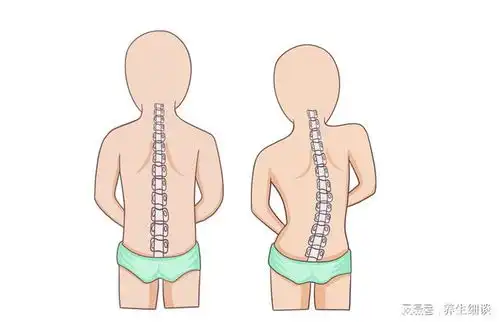

脊柱侧弯最佳睡姿vs最差睡姿

脊柱侧弯的正确睡姿

脊柱侧弯注意睡姿能矫正侧弯吗

万万没想到这种睡姿会导致脊柱侧弯

上海强直医院脊柱矫正中心告诉你正确睡姿避免脊柱侧弯

一女生睡姿不对致脊柱侧弯睡觉究竟侧卧好,还是平躺好

脊柱侧弯纠正大法多图详解,赶紧转走

体检发现脊柱有侧弯,该如何改善

值的医疗脊椎侧弯矫正一定要改变侧面姿势,否则徒劳无功